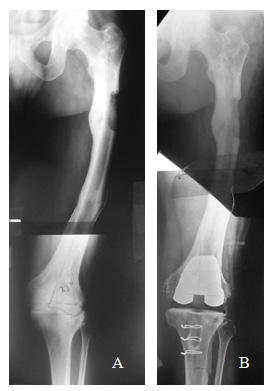

The causes of the deformity were: A- Post-traumatic in 8 patients (36.4 %): 3 due to malunion of femoral shaft fractures, 3 due to malunion of femoral supracondylar fractures and 2 nonunion of the proximal third of the tibia; B- Supracondylar Femoral osteotomy in 8 patients (36.4%): 7 varus (Figure 1) and 1 valgus; and C- Tibial osteotomy in 6 patients (27.2%): 3 Varus and 3 valgus osteotomies. We must point out that even if the majority of the valgus osteotomies of the proximal tibia create an extra-articular deformity, only those exceeding 10° have been included in this study.

Figure 1 A-70 year old man with valgus osteoarthritis of the right knee, a previous femoral varus osteotomy, an 11° femoral varus deformity and valgus anatomical axis of 13°. Note the limitation for using the femoral endomedular guide due to the deformity and the hardware. B- TKA with a valgus final axis of 3°. In this case we used an extra-medulary femoral guide. The femoral prosthesis stays centered in the epiphysis and appears as “not centered” with the femoral shaft.

There were 13 varus knees (average of intra-articular deformity of 9.2°) and 9 valgus knees (average of intra-articular deformity 16.6°). The extra-articular deformity was situated in the middle third of the femur in 3 patients (13.6%) (Figures 2 & 3), in the distal third of the femur in 11 (50%) (Figure 1), in the proximal third of the tibia in 6 (27.2%) and in the middle third of the tibia in 2 (9.1%). Regarding the type of deformity, all of the patients had a coronal deformity, 10 in varus (average 16.3°), 11 in valgus (average 14.4°) and 1 case with a medial displacement of the distal femoral segment of 3 cm. (Figure 3). In 6 patients, the deformity was biplanar, also with alterations in the sagital plane, 3 in flexion and 3 in extension, with an average of 19.7° and 8° respectively. No patients showed a significant rotational deformity.

Figure 2 Use of conventional X-rays as a puzzle to measure the limb`s axisA- 47 year old male showing a 2 site left femoral shaft deformity, consequence of a fracture. Valgus knee osteoarthritis, ROM 10° to 40°, femoral varus deformity of 18° and valgus anatomical axis of 23°. B- An All Poly TKA was made, obtaining a final valgus axis of 7°. In order to facilitate the access to the joint, an osteotomy of the tibial tuberosity was performed.